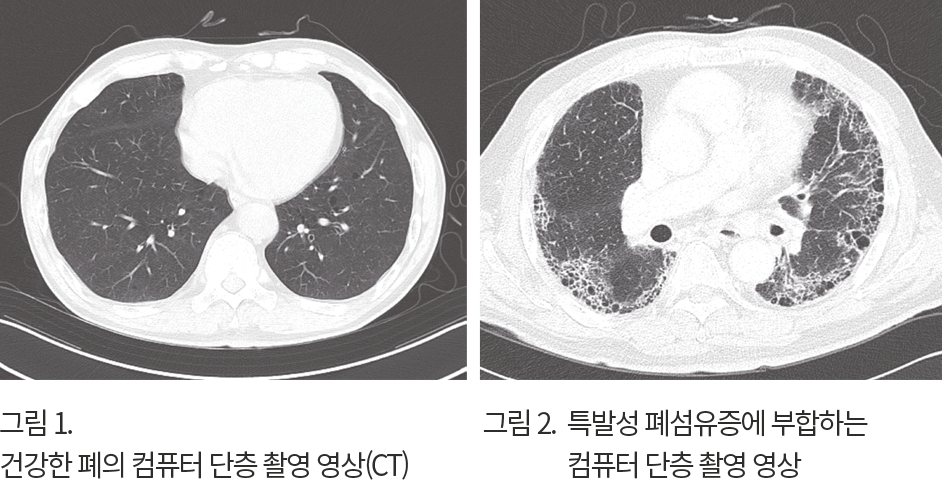

특발성 폐섬유증은 병력과 검사를 통해 진단합니다. 병력에서 특별한 원인 없이 마른 기침과 진행하는 호흡곤란이 있다면 간질성 폐질환을 의심합니다. 폐 청진을 하면 양쪽 아래 가슴에서 찍찍하는 소리가 들립니다. 기본적인 검사는 가슴 엑스선 사진을 촬영하며, 사진에서 양쪽 폐에 그물망 음영 같은 간질성 폐질환 의심 소견이 발견되면 다음으로 가슴 컴퓨터 단층 촬영(CT)을 시행합니다. 병력에서 특별한 원인이 없는 간질성 폐질환이 확인되고, 폐기능검사에서 폐활량과 폐 확산 능력이 감소하며, 가슴 컴퓨터 단층 촬영 소견이 특발성 폐섬유증에 부합하면 진단할 수 있습니다. 대부분의 특발성 폐섬유증은 조직검사 없이 위 검사로 진단되지만, 컴퓨터 단층 촬영 소견이 애매하거나 다른 질환이 의심되면 기관지 내시경이나 폐 조직검사 같은 추가 검사를 시행할 수 있습니다. 증상이 없고 폐 기능이 정상인 경우, 추적 관찰하면서 나중에 전형적인 소견이 보일 때 진단하기도 합니다.